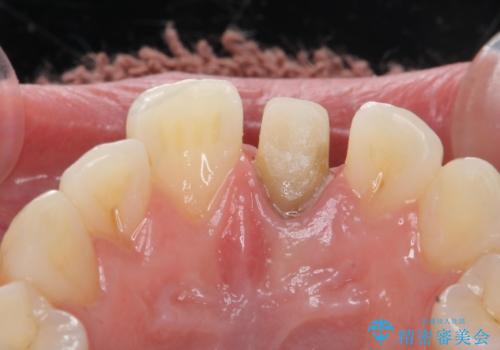

- 前歯の変色を主訴に来院された患者様です。

より審美的な修復を行いたいとのことであったため、ジルコニアクラウンでの修復を行います。

- 左上1 : 仮歯 / 11,000円、ジルコニアクラウン(スペシャル) / 154,000円 合計165,000円(税込)費用は治療当時の料金となります